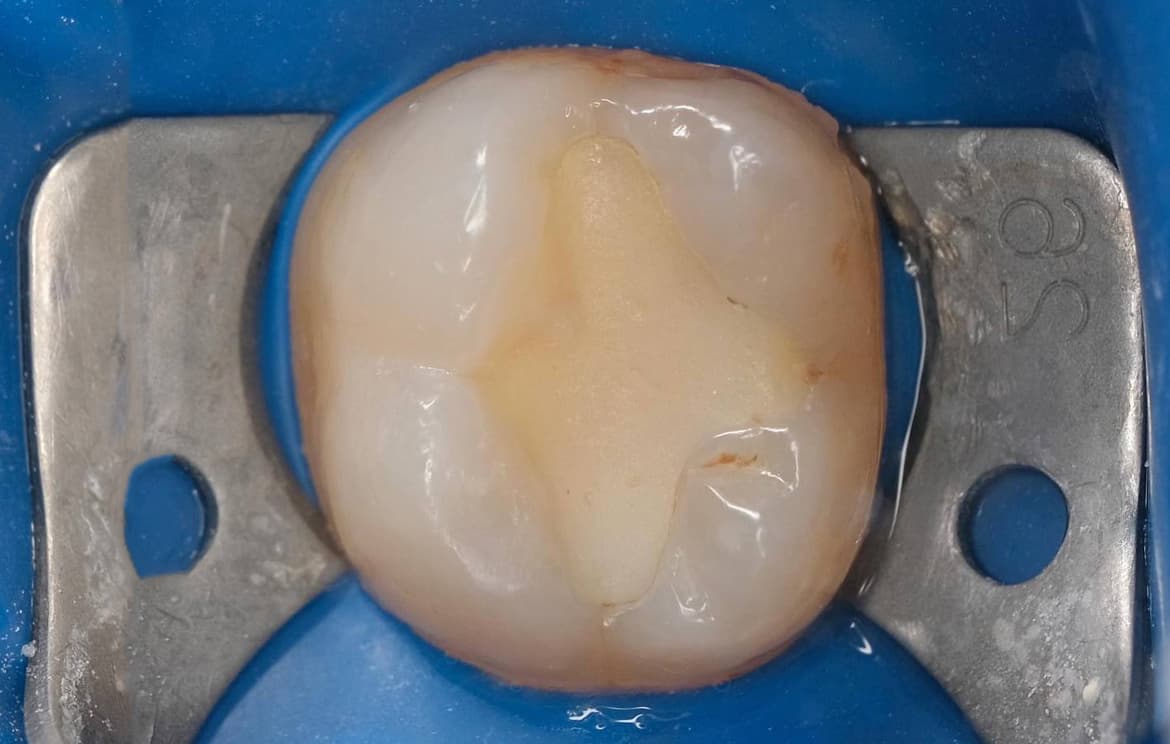

Наши работы